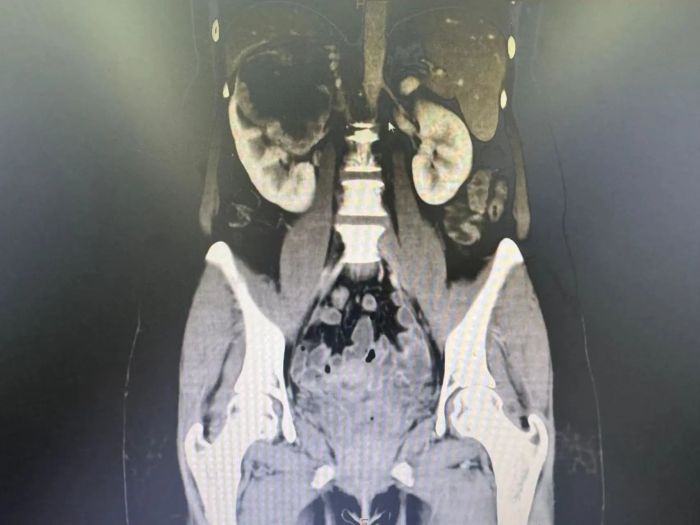

靶向联合免疫治疗后

完善相关靶向治疗及免疫治疗前检查后,排除用药禁忌症,申智勇博士团队予陈女士进行了规律、规范的肾透明细胞肾细胞癌靶免联合术前新辅助治疗,并做好肿瘤全程管理及追踪。用药治疗期间陈女士未感任何不适,没有严重不良反应。用药一周后再次复查下腹部CT平扫及下腹部CT增强,发现右肾肿瘤呈中心液化坏死,与肝脏界限明显清晰,肾门淋巴结较治疗前明显缩小。“可以手术”!在石家齐教授、申智勇博士的指导下,泌尿外科积极完善术前相关准备,同时请影像科、肝胆外科、胃肠外科、手术麻醉科、ICU、病理科、医务部多学科共同进行四级手术术前讨论,为了确保手术成功,团队制定了缜密的手术方案,在石家齐教授和申智勇博士的带领下,手术团队历经3个多小时,顺利完成了“经腹腹腔镜下右肾癌根治术+肾门淋巴结清扫术”。术后陈女士生命体征平稳,经精准治疗及精细术后护理,陈女士术后2天下床活动,恢复良好,右侧腰背部疼痛症状明显消失,现已经出院恢复正常生活。